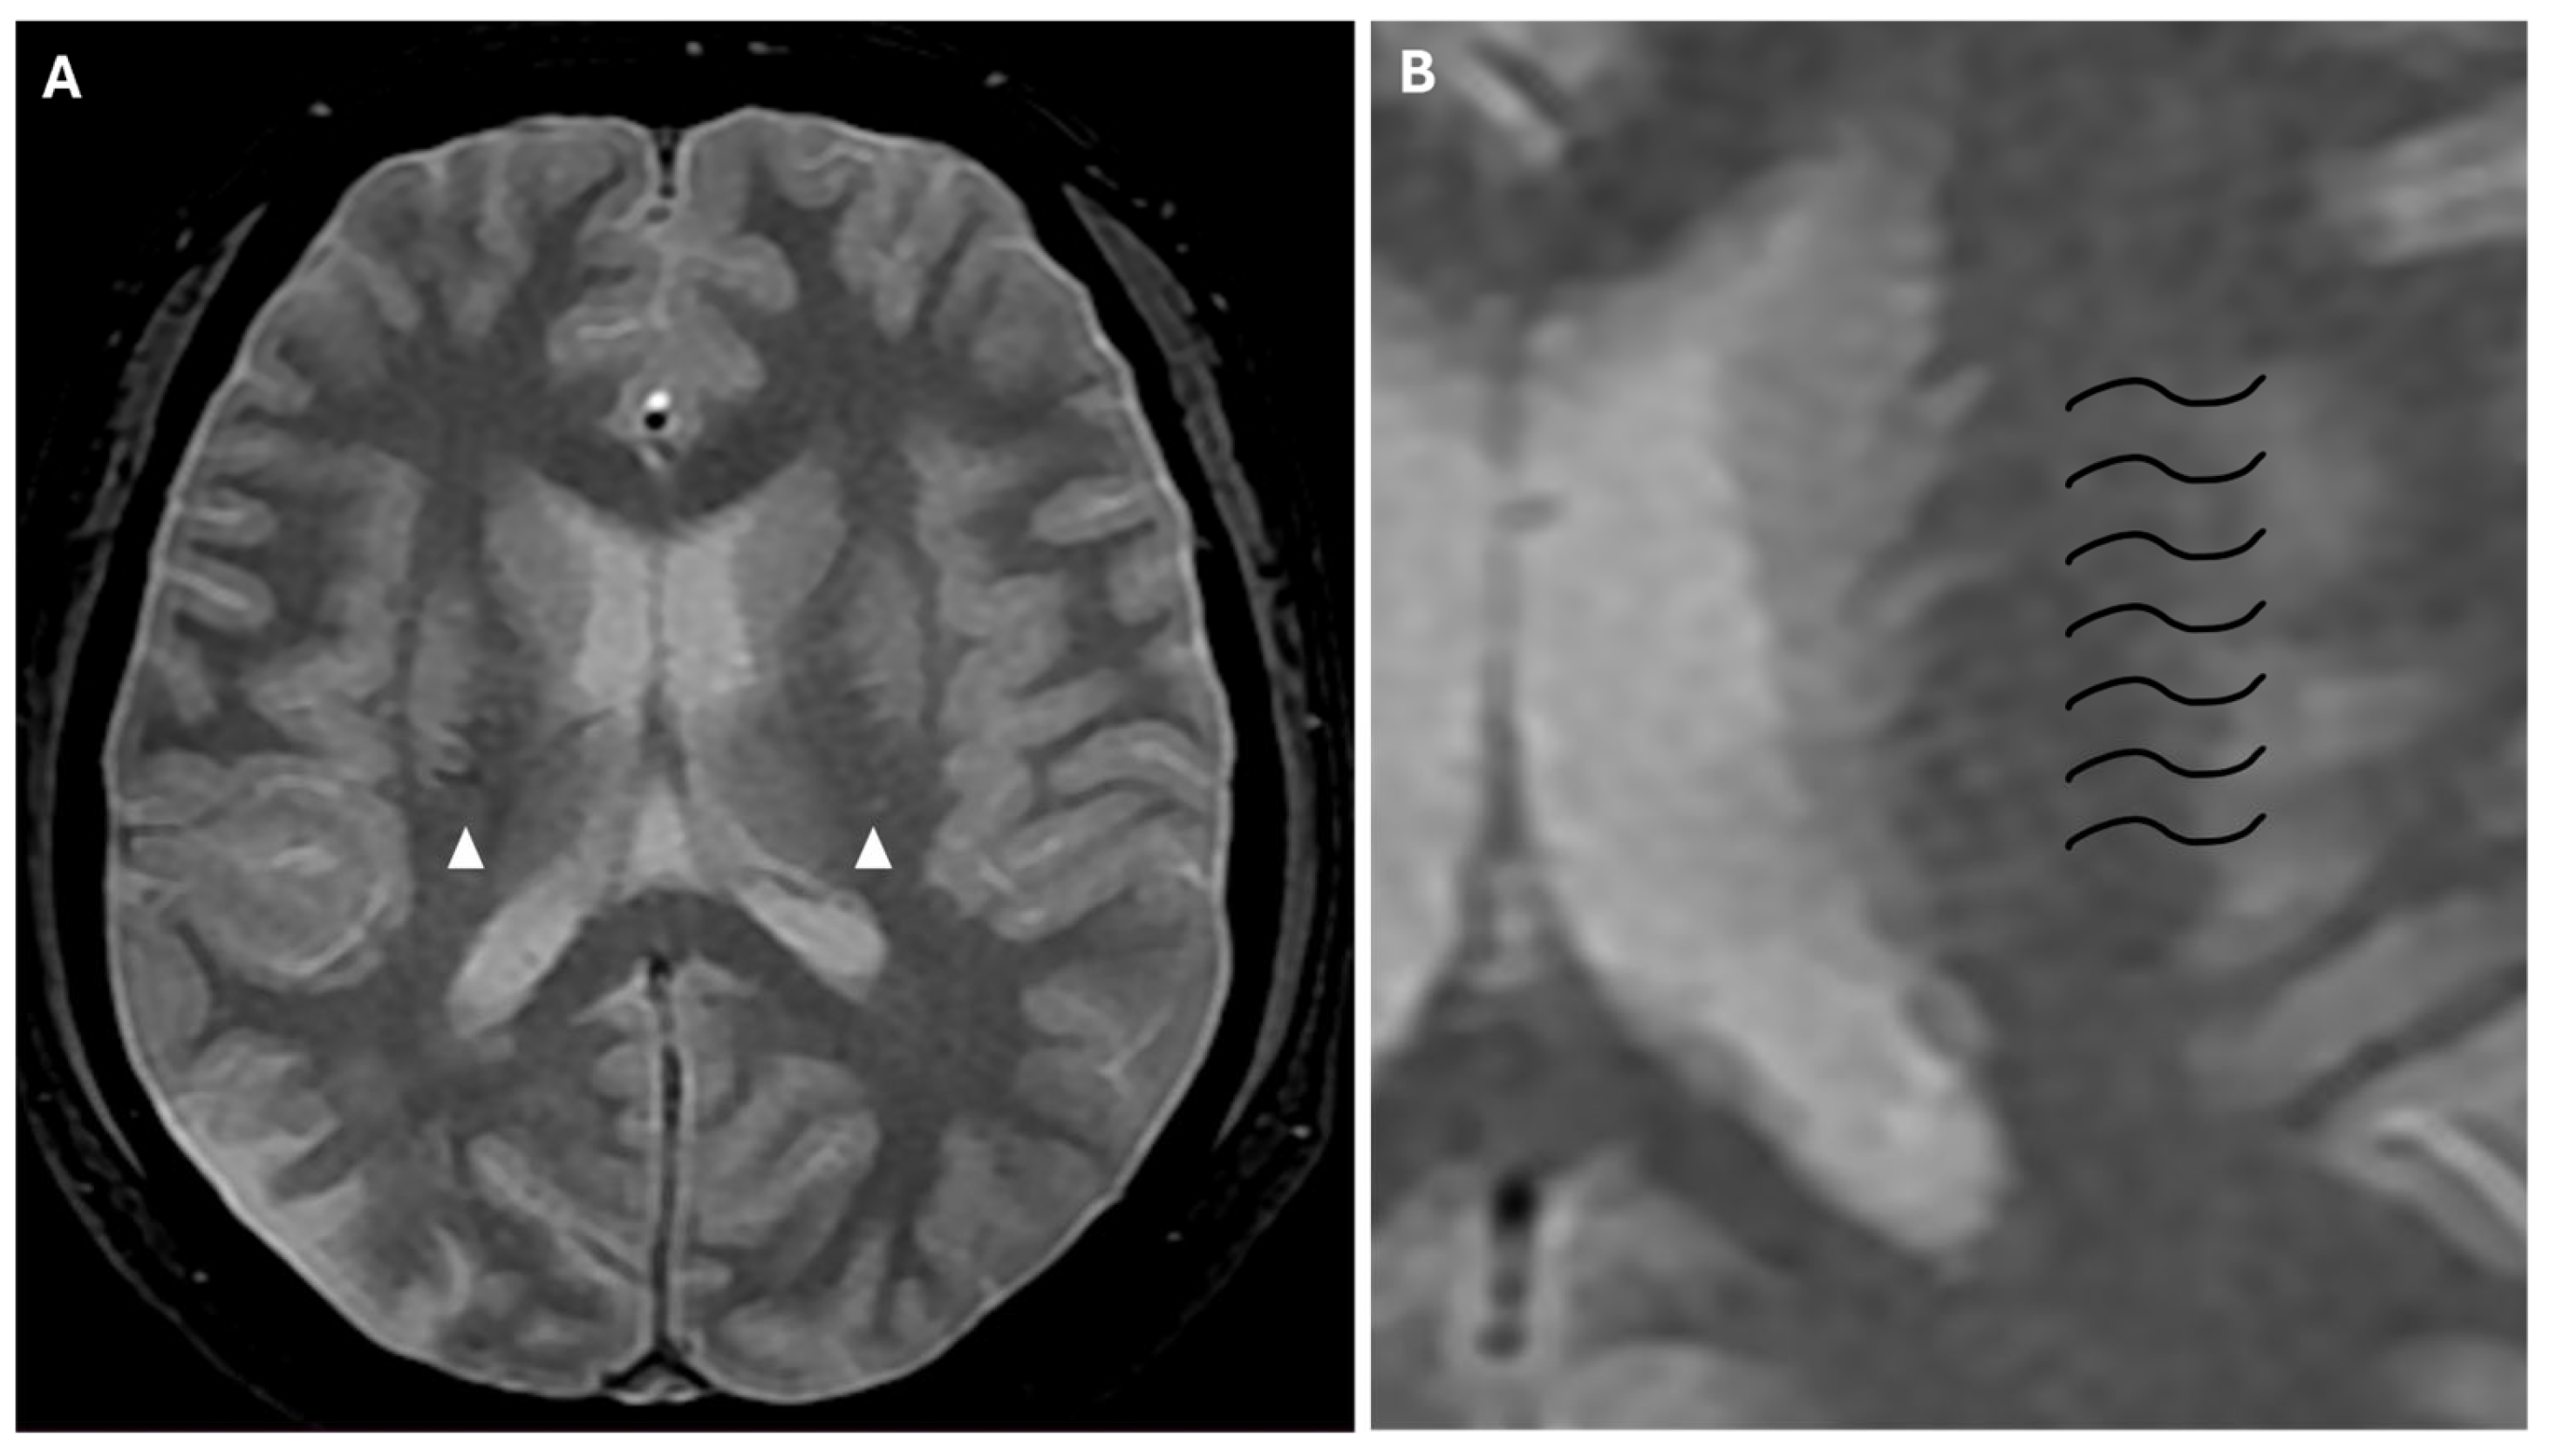

Another phenomenon that can be observed on FLAIR sequences is the “medullary streak” sign, which is characterized by a hyperintense streak oriented perpendicularly to the lateral ventricle (“periventricular medullary veins/FLAIR hyperintense streaks”); despite its etiology remaining ambiguous, the condition has been associated with ischemia and could represent collateral vasculature, stagnated cerebrospinal fluid, or vasogenic edema (Figure 7).

Figure 7. Axial (A) and coronal (B) 3d FLAIR sequences show a hyperintense streak area oriented perpendicularly to the right lateral ventricle (white arrows), representing the “medullary streak” sign. Note the right parietal subacute ischemic lesion (white arrowhead).